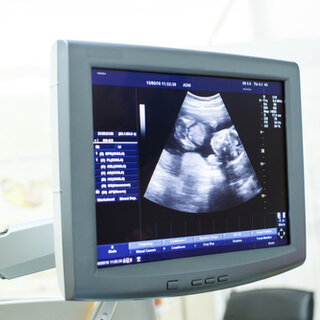

5. التصوير بالموجات فوق الصوتية

تُعد متابعة التبويض بالتصوير بالموجات فوق الصوتية أحد الطرق نادرة الاستخدام؛ لأنها مكلفة وتستهلك الوقت، ولكنها تساعد في تحديد فترة التبويض من خلال توضيح بعض التغيرات، مثل: تغير حجم الجريب (Follicle)، ووجود السوائل في الحوض.